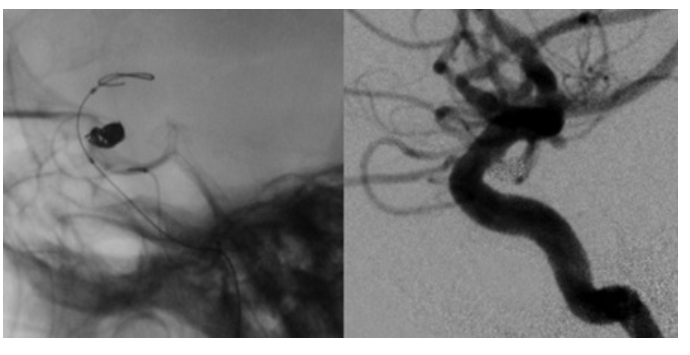

一方、②の血管内治療は、脳の血管の内側から動脈瘤にコイルをつめる手術法で、最近発展してきた技術です。細いカテーテルというチューブを動脈の内側から動脈瘤内に誘導し、細く柔らかい金属製のコイルで動脈瘤をつめます。頭を切らずに動脈瘤をつめることができることから急速に普及し始めています。不十分な閉塞に終わった症例では、瘤が再発することも報告されており、慎重な経過観察が必要となります。

治療は全身麻酔で行います。鼠径部からカテーテルという管を動脈瘤近くまで進めて留置します。そこからさらに細いマイクロカテーテルを操作して動脈瘤内に誘導、留置します。留置の際にバルーンなどの補助を使って行うこともあります。

そこからプラチナでできた柔らかいコイルを動脈瘤の中に詰めていきます。動脈瘤内にコイルが行きわたり、瘤内に血流がなくなれば手術終了です。瘤内に血流が行かなくなるので出血のリスクは格段に下がります。